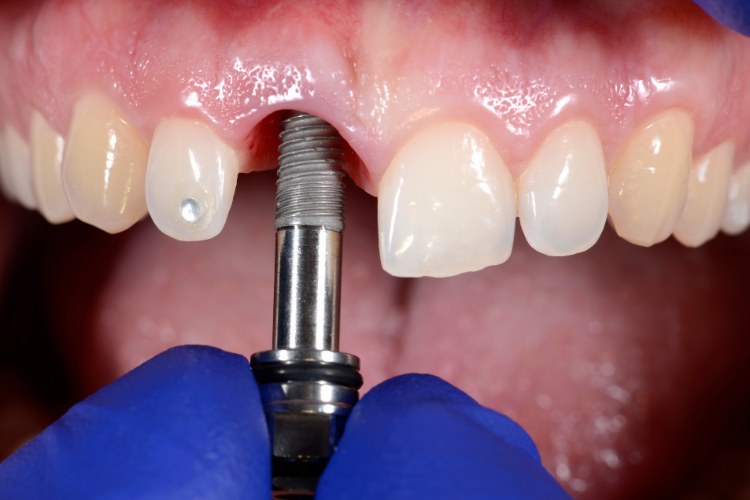

Impressions of the abutment and surrounding teeth are taken to create a custom crown that matches the size, shape, and color of the natural teeth. The crown is typically made of materials such as porcelain or ceramic.